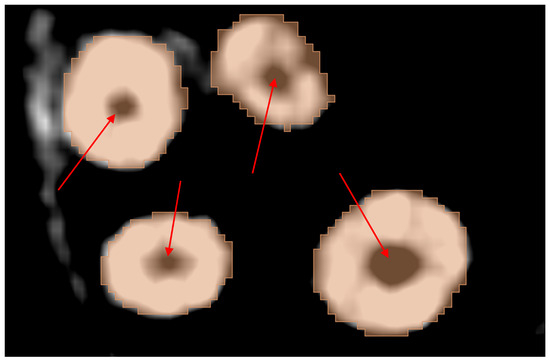

3.5. Results of Dataset 3